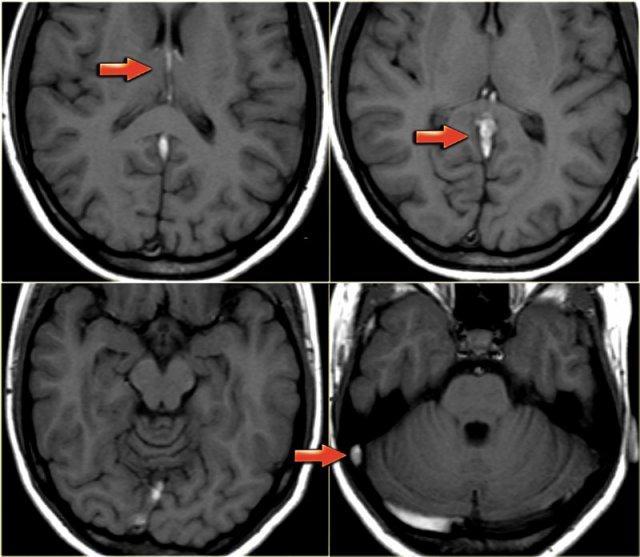

Mất tín hiệu trống dòng chảy bình thường trên MRI (2)

Các hình ảnh bên trái cho thấy tín hiệu cao bất thường trên chuỗi xung T1W do huyết khối.

Huyết khối lan rộng từ các tĩnh mạch não sâu và xoang thẳng đến xoang ngang và xoang sigma bên phải.

Lưu ý tín hiệu trống dòng chảy bình thường ở xoang ngang trái trên hình dưới bên phải.

Sự vắng mặt của tín hiệu trống dòng chảy bình thường trên MRI có thể rất hữu ích trong việc phát hiện huyết khối tĩnh mạch, nhưng có một số bẫy chẩn đoán mà chúng ta sẽ thảo luận sau.

Dòng chảy chậm trong tĩnh mạch có thể gây tăng tín hiệu trên T1W.